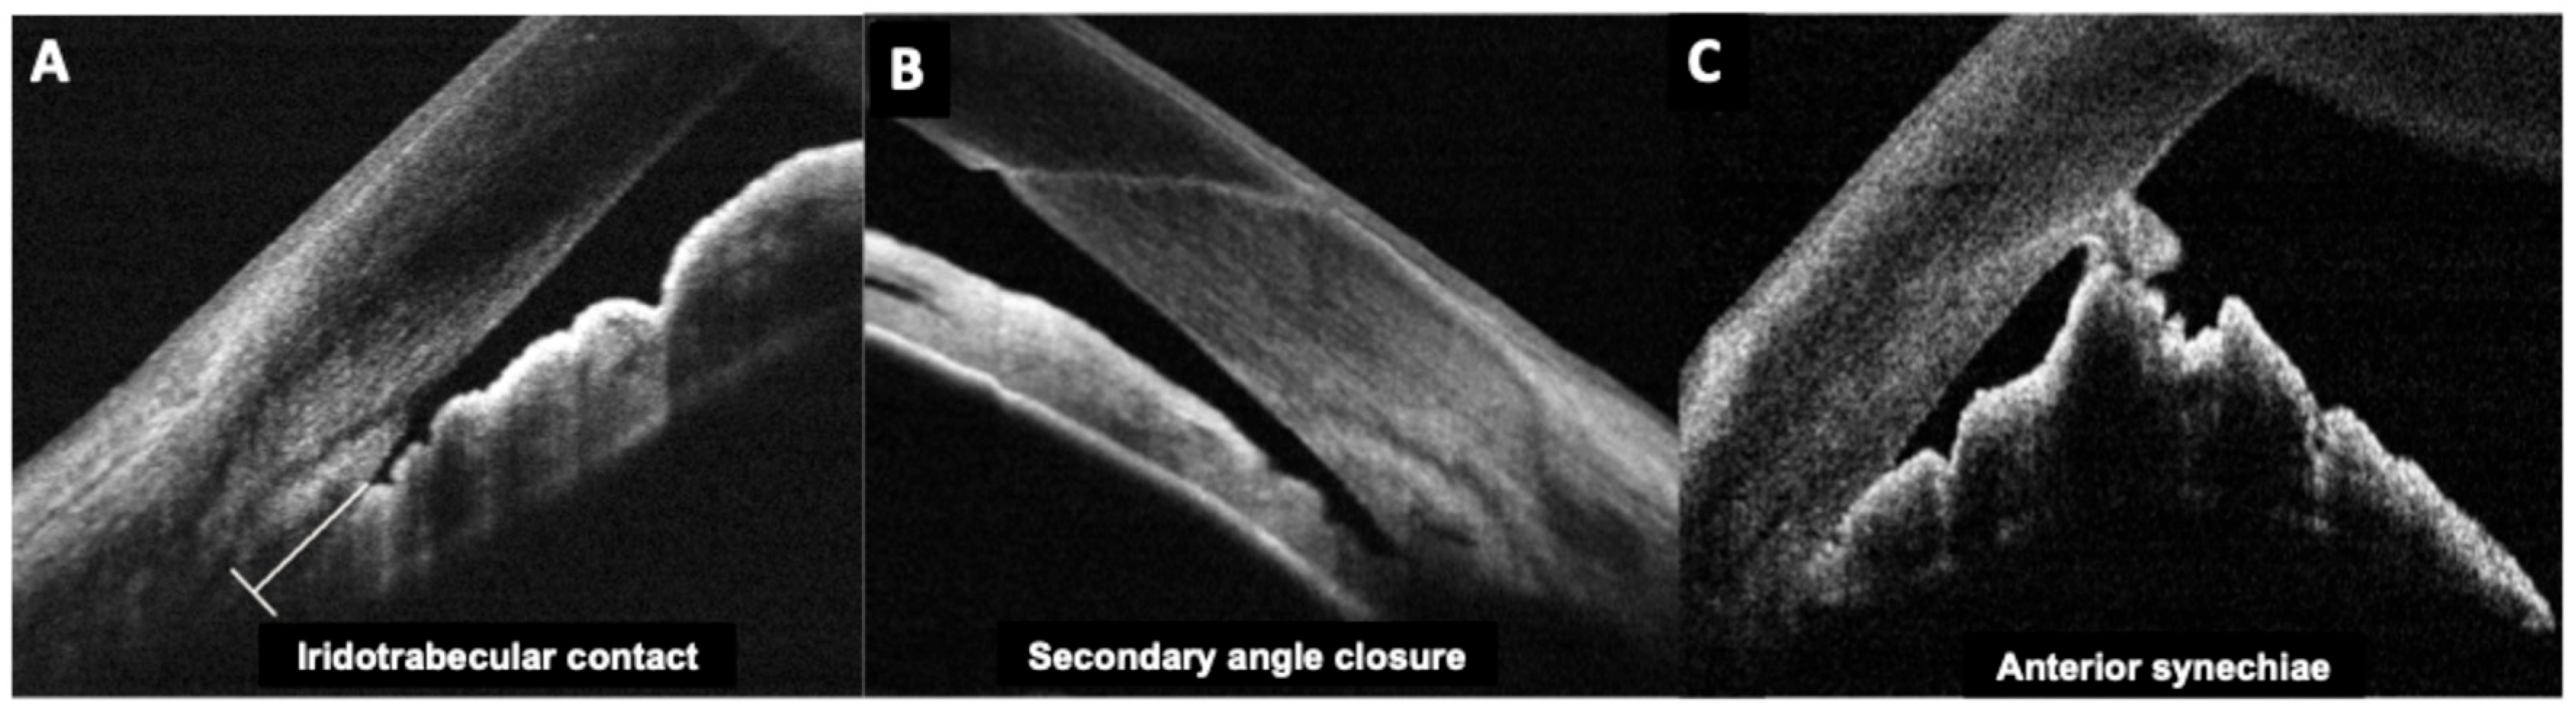

2.3.4. Angle Anatomy

Fourier-domain and swept-source anterior segment OCT can image the iridocorneal angle in detail. After pIOL implantation, angle anatomy often changes: posterior chamber ICLs typically cause a mild reduction in angle width and volume because the iris is slightly pushed forward by the ICL (Figure 2). A study revealed postoperative angle opening distance decreased by ~20–25% after ICL, though the angles generally remained open in appropriately selected eyes [27]. Similarly, our group determined iridocorneal angle changes prospectively in ICL patients, indicating initial angle narrowing of 39–45% which was stable beyond 1 month postoperative [39].

Clinicians have reported using OCT to differentiate pupillary block from other causes of high intraocular pressure. In pupillary block, the OCT shows the iris bowed forward in a classic “iris bombe” convexity contacting the lens or ICL, with a deep posterior chamber and shallow anterior chamber. Anterior segment OCT can confirm iris bombe configuration, even when a hazy cornea or a small pupil limits the gonioscopic view [44]. Anterior segment OCT allows for a precise evaluation of hyperopic ICL cases, which usually present with narrower baseline angles, as well as for monitoring the dynamic changes in vault and angle configuration that occur with miosis and mydriasis (Figure 3 and Figure 4).

Figure 3. Preoperative and postoperative angle opening after hyperopic implantable Collamer lens (ICL) implantation.

Figure 4. Change in the vault during miosis and mydriasis after myopic (upper rows) and hyperopic (bottom rows) implantable collamer lens (ICL) placement.